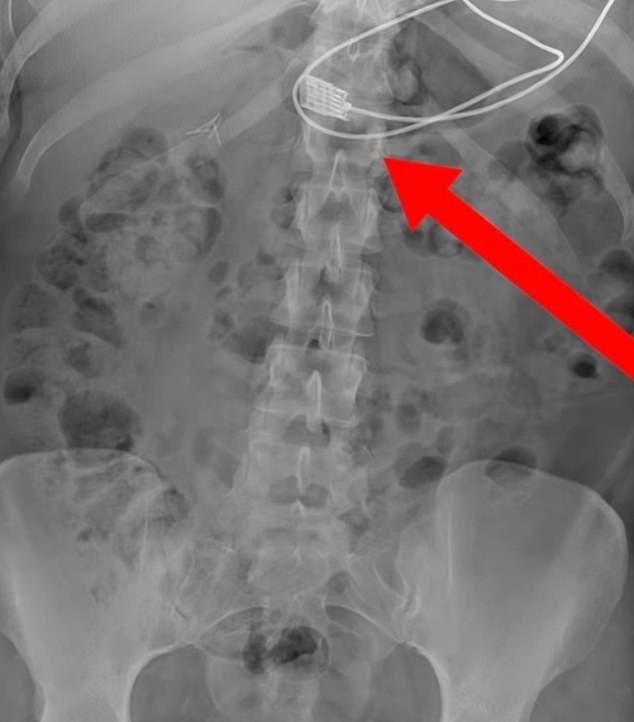

1m 길이의 휴대전화 충전 케이블을 삼킨 여성의 엑스레이 사진이 공개돼 충격을 주고 있다.

그는 1m 길이의 아이폰 충전기 케이블을 삼킨 후 식도에 케이블이 박혀 질식하기 시작했고, 스스로 응급 구조대에 전화를 걸었다.

레디 투 레스큐는 케이블은 성공적으로 제거됐으며 여성은 완전히 회복됐다고 전했다. 여성이 케이블을 삼킨 구체적인 이유에 대해서는 알려지지 않았다.